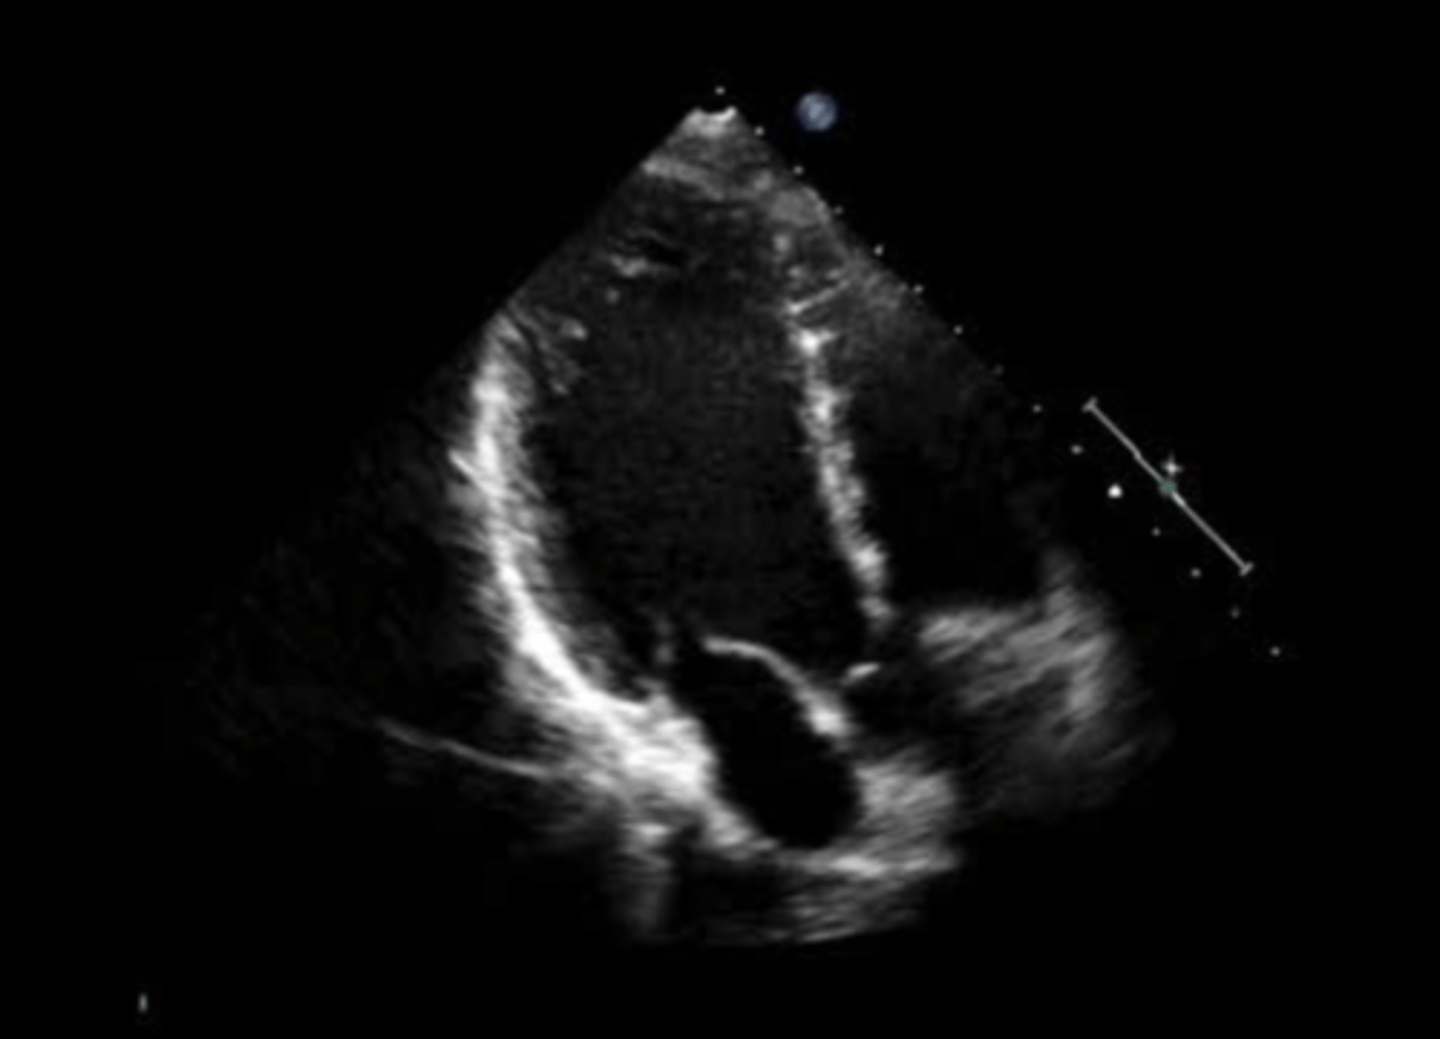

anterior mitral valve leaflet

top leaflet

posterior mitral valve leaflet

bottom leaflet